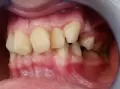

Мне 18 лет. Две недели назад заметила, что вверху за правым клыком растет зуб. Была в ужасе, ведь все зубы молочные у меня выпали. Сделала панорамный снимок, посоветовали вытягивать ретинированный зуб. Но врачи не смогли определиться какой зуб - молочный клык или резец.

Возможно ли вытянуть клык, который стоит напротив резца и расположен на расстоянии более 1 см от своего места в зубном ряду?

Ретенированный зуб можно вытянуть с помощью брекет-системы, а также не исключено, что он прорежется самостоятельно. И его останется установить на свое место.